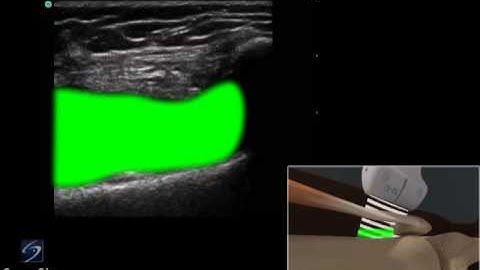

How to: Ultrasound Guided Knee Injection Scanning Technique